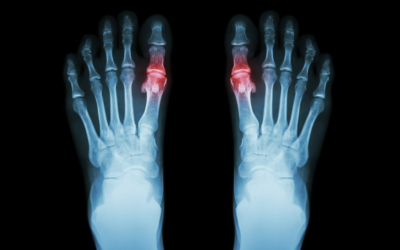

Why Do Bunions Get Worse Over Time?

Bunions, also called Hallux valgus, are often painful protrusions at the bottom of your big toe. They can cause a wide range of issues such as bursitis, hammertoe, and metatarsalgia, which is why you should contact your local Victoria, Kelowna, or Nanaimo foot...